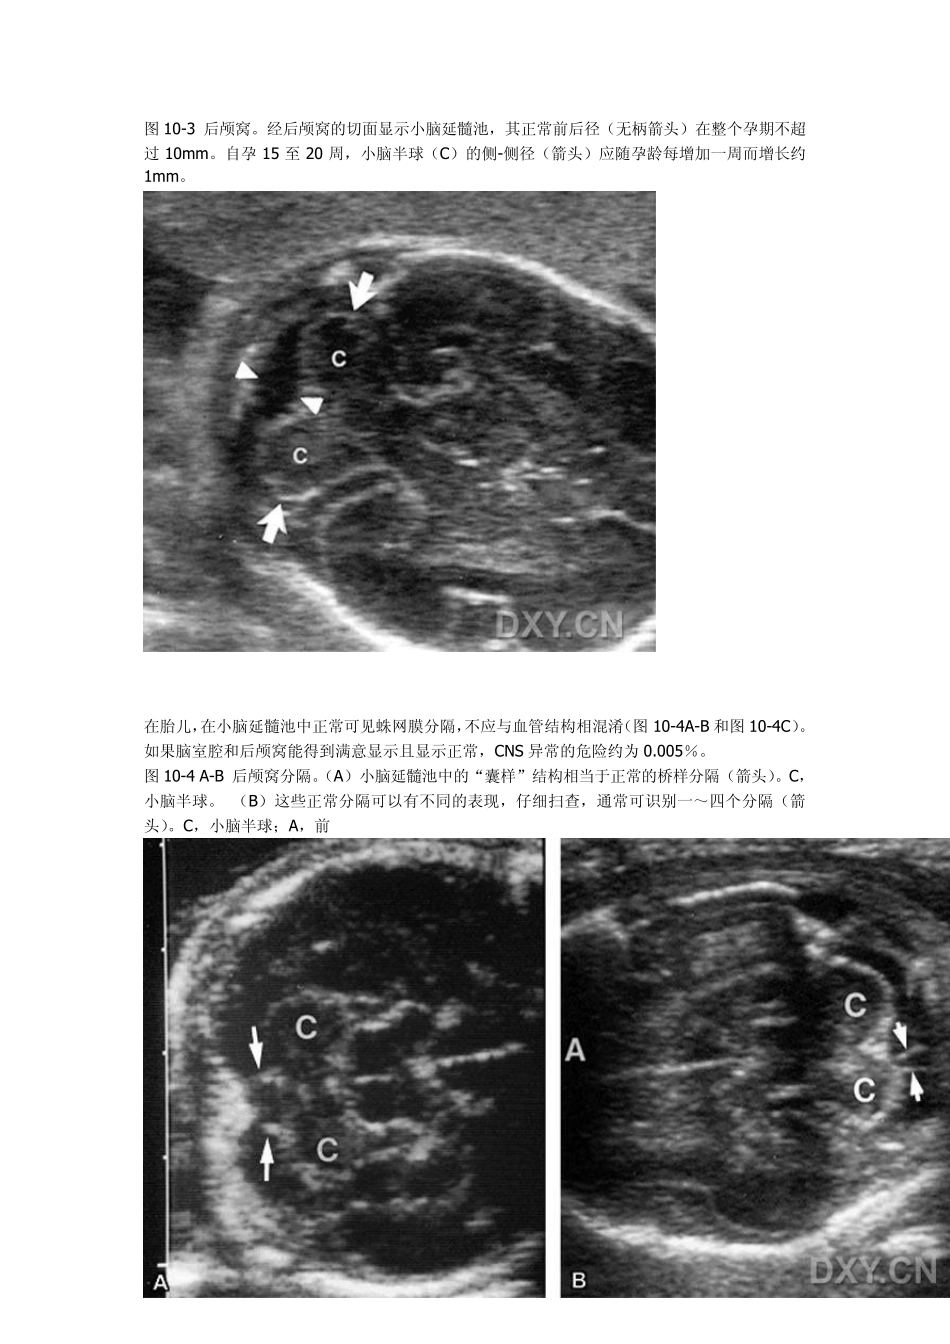

产科超声---胎儿头部和脑 [精华] 正常解剖 作为产前超声检查的方针之一,对胎儿中枢神经系统(CNS)包括脑室、后颅窝(包括小脑半球和小脑延髓池)、和脊柱的评估已受到重视。其他的研究者认为以综合方法评估妊娠第二、三期的胎头包括显示(1)脑室腔,(2)小脑延髓池,(3)透明隔腔。这三个解剖区域在标准成像切面上的显示排除了大多数颅内异常的诊断。 脑室腔 “下侧”脑室腔在99%的正常胎儿可以显示。脑室腔在经胎儿头盖骨的标准横切面上显示最佳。在此平面,脑室腔体积在妊娠第二、三期维持恒定。正常脑室腔平均径线 6~7mm。10mm 的测值超出平均值 4 个标准差,因而被认为是正常和异常脑室腔大小的分界(图 10-1A-B,图 10-1C,图 10-2)。最近,Alagappan 和同事研究了500 例正常胎儿的大群体,发现下侧脑室腔的均值是6.6mm。但此研究群体的标准差大,为1.4mm。因此,用 2.5 个标准差,这些研究者确立了10mm为这一群体的正常上限。 研究资料已经证明了在整个孕期中用一种成角技术显示近侧即“上侧”脑室的可行性。上侧脑室体的正常测值在整个孕期维持不变,相当于均值加 2.5 个标准差的正常上限是 8mm(见图10-1A-B,图 10-1C 和图 10-2)。 图 10-1A-B 孕 21 周的正常脑室。(A)实时图像显示脉络丛充盈远离探头的脑室的三角体部(箭头)而未显示近探头的脑室。A,前;T,丘脑;空心箭头,大脑外沟池(sylvian cistern);弯箭头,透明隔腔。 (B)如图所示,探头扫查面的位置是通过颞骨区扫查颅盖,此切面是成角的,与通过离探头较近的脑室的扫查面无关。 图-10-1C 实时图像显示“上侧”脉络丛(弯箭头)充盈侧脑室。可见到“上侧”侧脑室的内、外侧壁(箭头)。 图10-2A-B 正常脑室:下侧和上侧。(A)胎儿脑部实时超声扫描显示了经透明隔腔(弯箭头)和脉络丛充盈侧脑室三角体(无柄箭头)的切面。上侧侧脑室未显示。在整个孕期侧脑室三角体自内侧壁至外侧壁的测值应小于 10m m 。A,前。 (B)用成角技术,显示脉络丛充盈侧脑室(无柄箭头)。在整个孕期,上侧侧脑室体的内侧壁至外侧壁径线应小于<8m m 。A,前。 小脑延髓池 后颅窝横切面的图像是由从用于显示脑室腔的切面向尾端偏角调节而获得的。这一途径显示脑干和小脑蚓部,其由小脑延髓池描绘出轮廓。在中线处自小脑蚓部后缘至枕骨内壁所测得的前后径约为 5m m 。小脑延髓池深度最大径线应不大于 10m m ,且不小于 2m m 。...